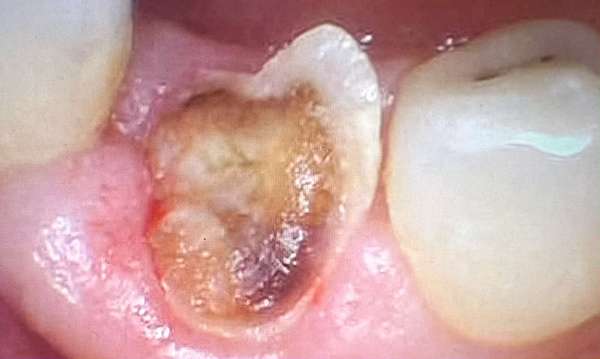

Removed all decay and placed a large tooth colored filling.

Before

After